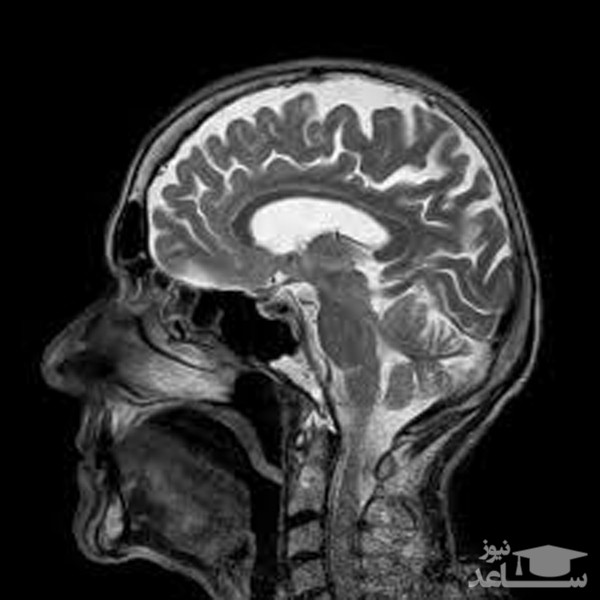

ساعد نیوز: این فیلم توسط پروفسور جینس فراهام فیزیک دان وزیست شناس آلمانی ساخته شده فیلم با استفاده از تکنولوژی (MRI )هنگام حرف زدن و آواز خواندن گرفته شده است.